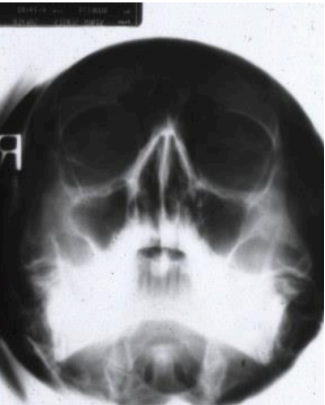

purpose of this radiograph

to view max sinus (waters projection)